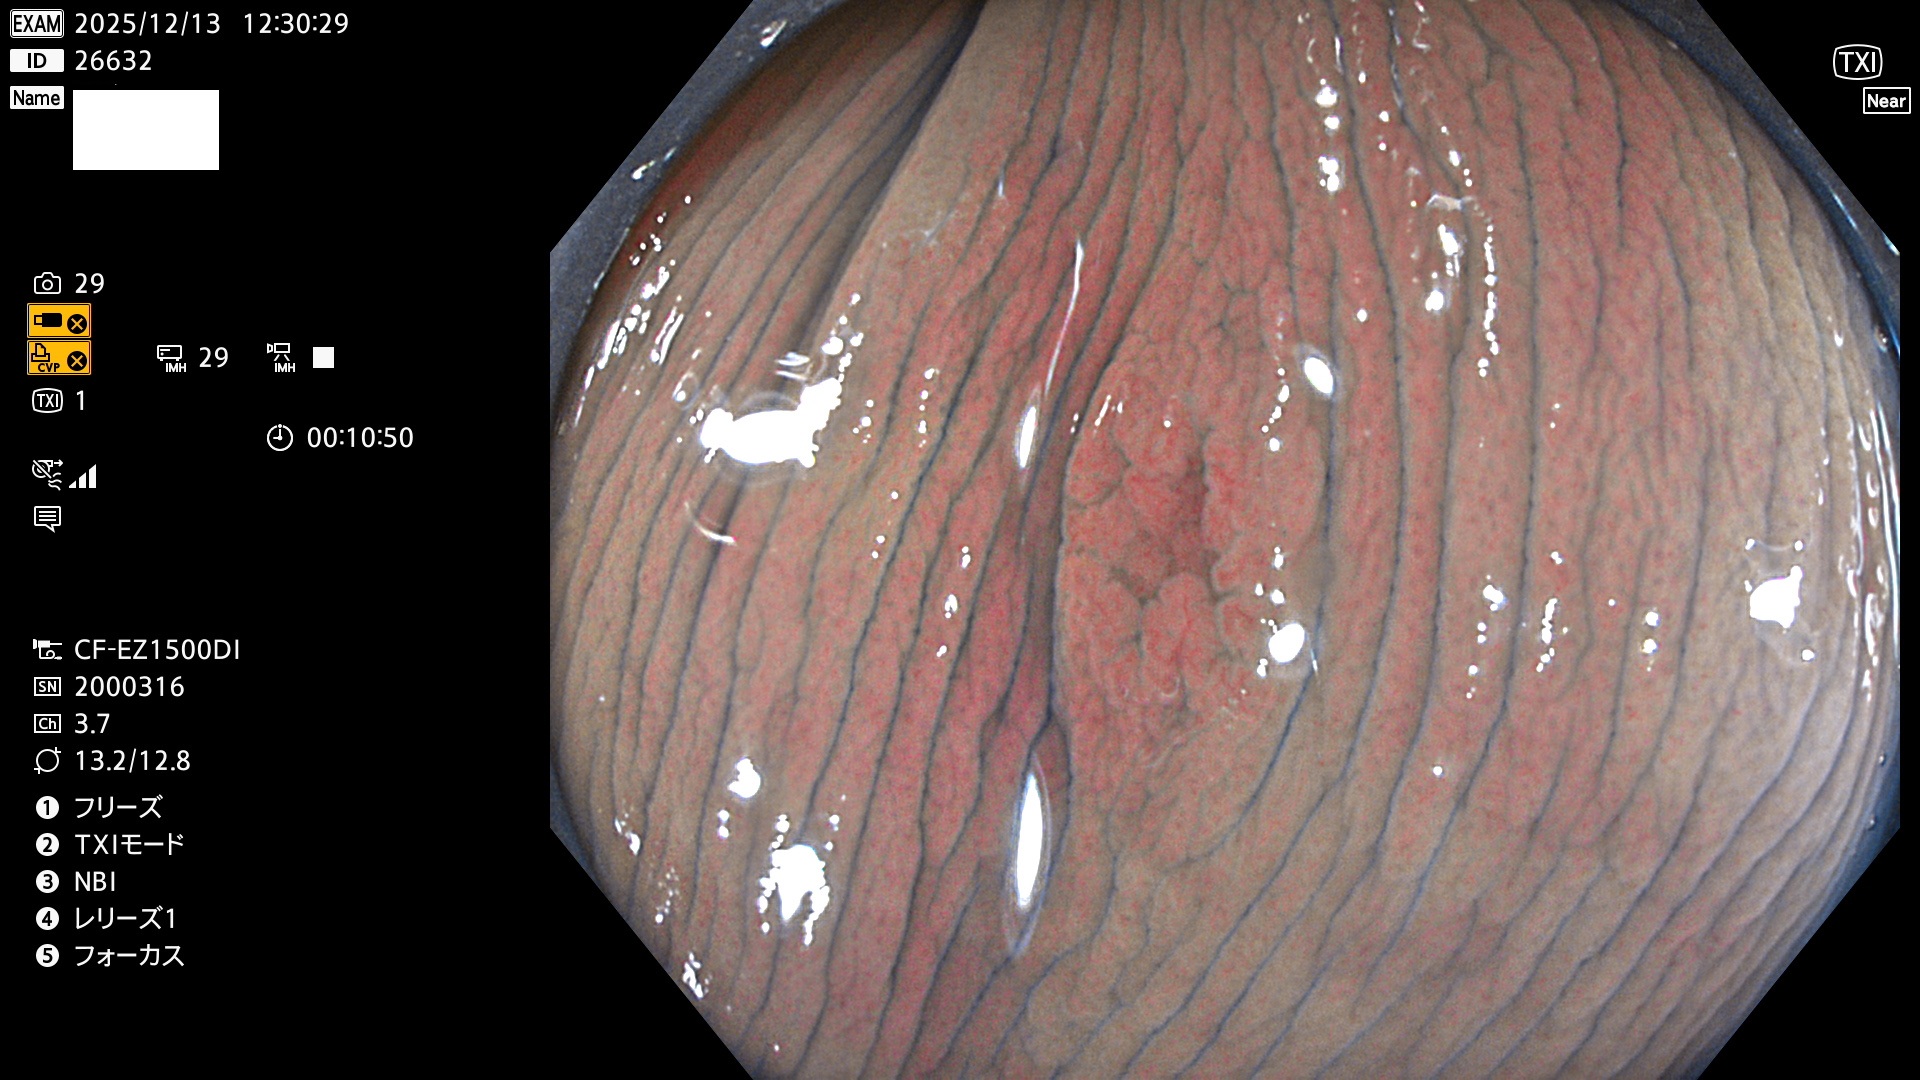

完全に平坦な物をUb、陥凹している物をUcと呼びます。Ubは認識が困難で、Ucはびらん(炎症)と紛らわしいために見落とされやすく、「内視鏡後・大腸癌」の原因になります。

専門的)Uc=De Novo癌? 内視鏡の解像度が低かった時代、このような説もありました。しかし今日の高精度内視鏡では良性の微小なUc型腺腫(APC遺伝子異常の腺腫)が日常的に見つかります。Ucこそが多段階発癌(Adenoma-Carcinoma Sequence)のMain Routeです。

毎週の検査(木・金・土・日)に発見されたUbとUc型・腺腫を、その週の日曜の夜にUPし1週間、提示します。

2025年11月27日〜12月7日の7日間(70件)で6個 (Uc_ADR=6個/70人=9%)